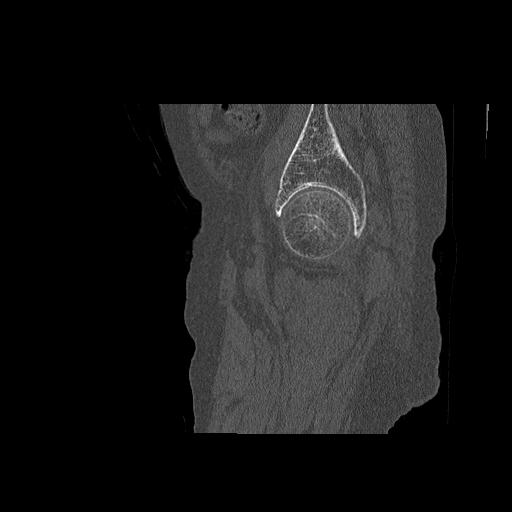

110286 2/17 股関節 2R 74歳女性 右人工骨頭

82084 1/14 1/20 股関節 2R 78歳男性 右人工骨頭

102811 1/13 股関節 2R 1/19 2R 80歳女性 右DHS